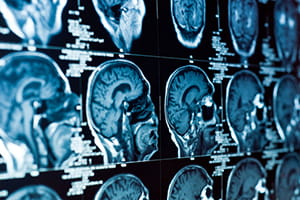

Both Morton Plant Hospital and St. Joseph’s Hospital utilize the latest advances technology for neurosurgical patients, including intraoperative magnetic resonance imaging (iMRI). This sophisticated imaging technology is used by neurosurgeons during procedures, allowing our doctors to take the highest quality imaging studies as they operate.